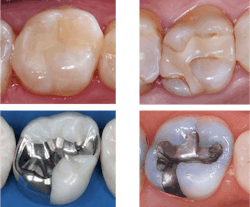

General dentists place numerous composites every day. The clinical longevity of composites is well known to be far shorter than that of amalgam restorations (figure 1). Several reasons relate to their short lifespan, including 2% shrinkage producing microscopically open margins on all restorations, no cariostatic activity provided by composite materials, inadequate curing accomplished by many dentists, occlusal wear, and other issues.

Since composite restorations are the most-used dental restoration type, and their inadequacies are obvious, this topic should be the highest priority for companies producing these products and for government agencies funding research. Our patients need nonshrinking, cariostatic, esthetic materials providing long-term service immediately!